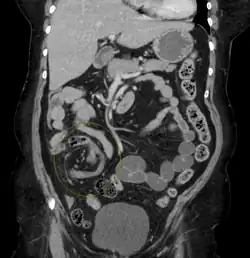

Diagnostic methodMedical imaging (plain X-rays, GI series, CT scan)[1]

Risk factors include a birth defect known as intestinal malrotation, an enlarged colon, Hirschsprung disease, pregnancy, and abdominal adhesions.[1] Long term constipation and a high fiber diet may also increase the risk.[3] The most commonly affected part of the intestines in adults is the sigmoid colon, with the cecum being the second most affected.[1] In children the small intestine is more often involved.[5] The stomach can also be affected.[6] Diagnosis is typically with medical imaging such as plain X-rays, a GI series, or CT scan.[1]

After taking a thorough history, the diagnosis of colonic volvulus is usually easily included in the differential diagnosis. Abdominal plain x-rays are commonly confirmatory for a volvulus, especially if a coffee bean sign is seen. These refer to the shape of the air-filled closed loop of the colon, which forms the volvulus. Should the diagnosis be in doubt, a barium enema may demonstrate a "bird's beak" at the point where the segment of proximal bowel and distal bowel rotate to form the volvulus.

This area shows an acute and sharp tapering and looks like a bird's beak. If a perforation is suspected, barium should not be used due to its potentially lethal effects when distributed throughout the free intraperitoneal cavity. Gastrografin, which is safer, can be substituted for barium.